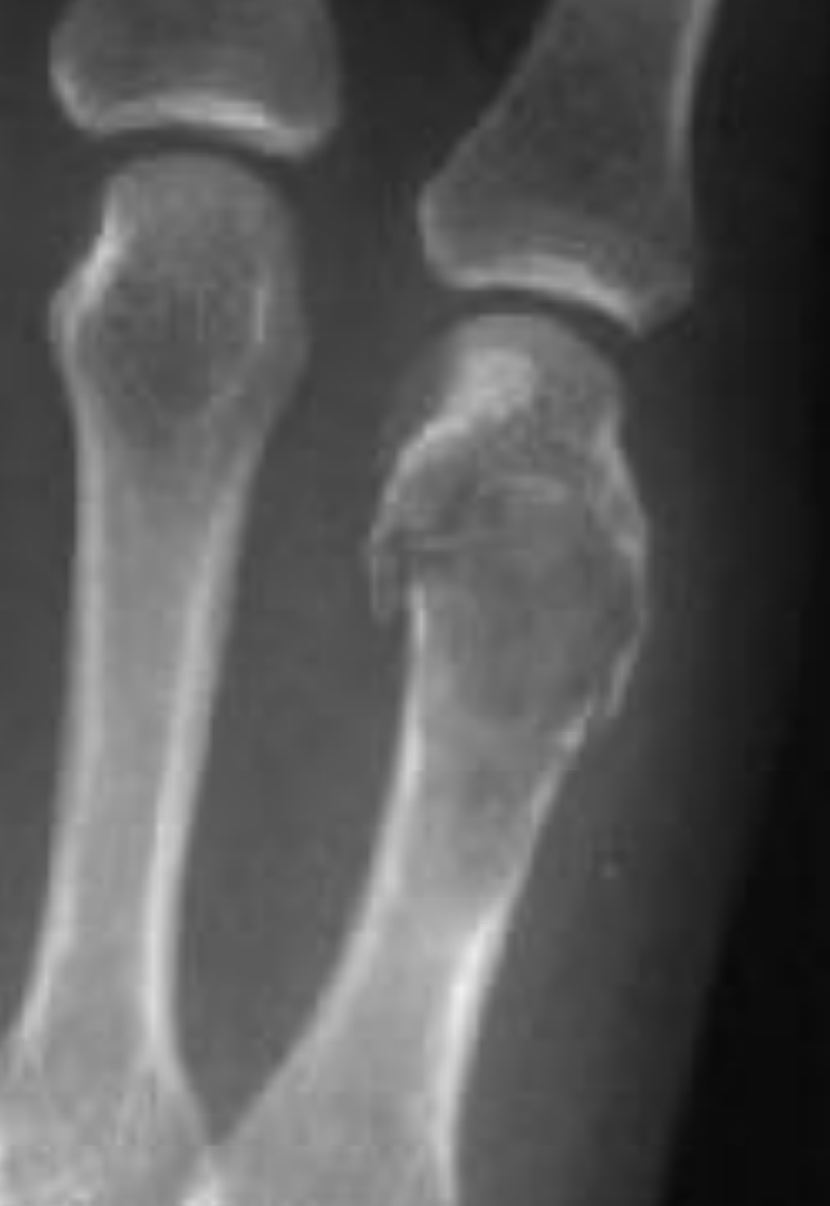

X-ray shows a Lytic lesion

Cotton wool calcification

Expansile and O ring sign - what is the likely diagnosis?

A

Enchondroma

Can overall look malignant on X-ray